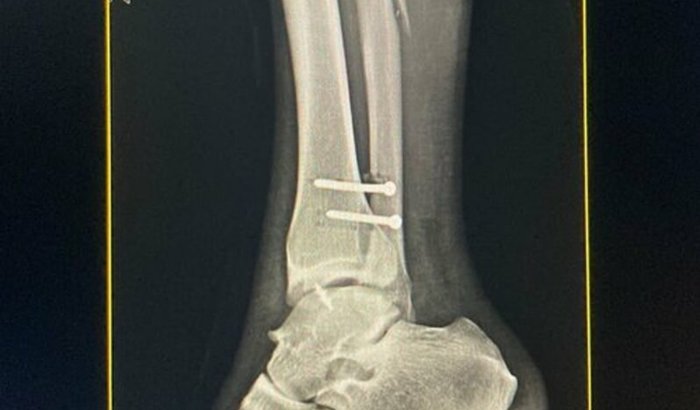

Há 6 meses tive uma fratura trimaleolar no tornozelo e no terço distal da fíbula após uma grave queda de skate.

Fiz uma abordagem via sus e não obtive o sucesso que esperava…

Estou com início de artrose degenerativa no tornozelo, precisarei fazer uma nova cirurgia de osteotomia para sanar o processo de desgaste de cartilagem.